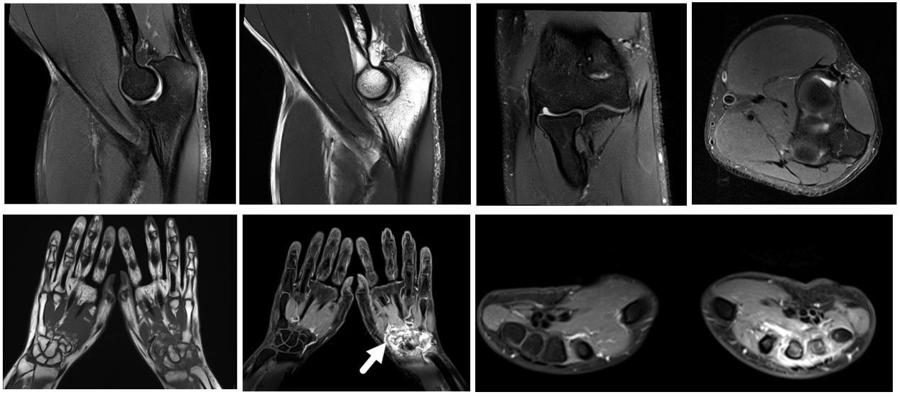

骨肌系统--UltraFlex small 18与BLADE技术相结合,有助于去除运动伪影,提高小关节成像效果与效率。